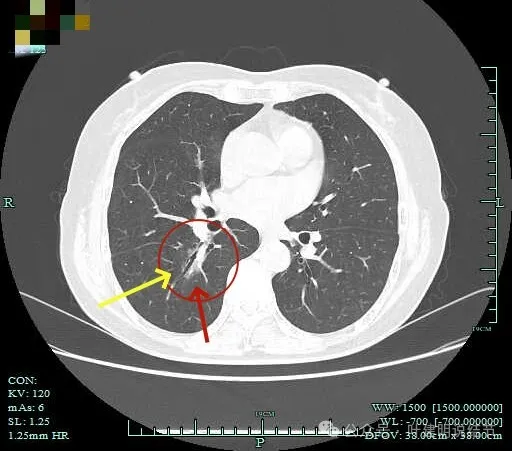

灶内血管走行,轮廓与边界清楚。

边缘有毛刺征!

沿支气管走行方向延伸,磨玻璃密度,且支气管内壁显得毛糙。